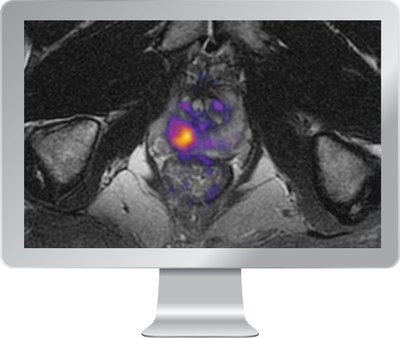

HealthLytix Receives FDA Clearance for Breakthrough Prostate Imaging Solution, RSI-MRI+

SAN DIEGO, Nov. 26, 2019 /PRNewswire/ -- HealthLytix (www.healthlytix.com), a healthcare technology company developing new advances in genetics and medical imaging to improve screening and early…